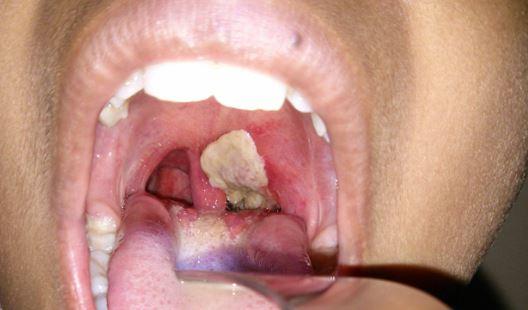

Diphtheria

Diphtheria, caused by a toxin produced by Corynebacterium diphtheriae, is a vaccine-preventable disease covered by one of the vaccines provided routinely through Nigeria’s childhood immunisation schedule.